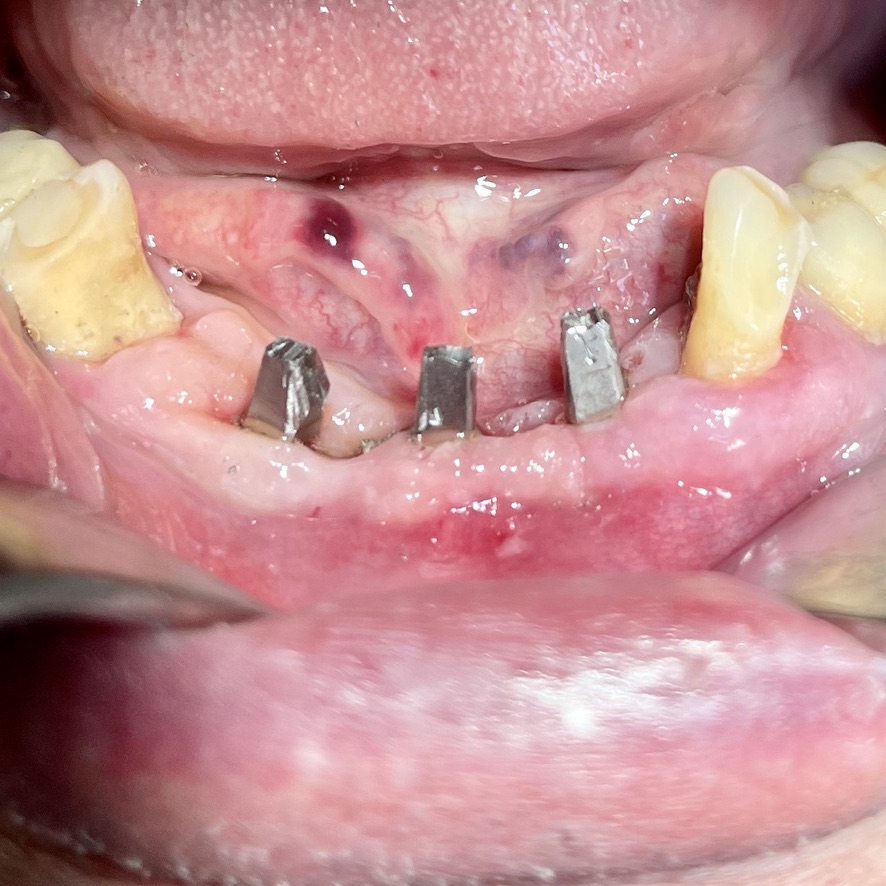

CLINICAL CASE combined with news n.6. Rehabilitation of 04/28/2021

In particular, I consider the following aspects to be significant:

• 10 Severe periodontal disease of the lower sector

• 12 Implant failure of lower Tramonte implant, implant prior to 2004, in the context of general periodontal disease

• 13 The insertion of the three implants did not involve bone or connective tissue grafts

• 14 It did not make detachments necessary

• 15 It was not necessary to isolate the emergencies of the inferior alveolar nerves

• 16 Since we are dealing with high-density bone, we resorted to the helical drill, an instrument rarely used by us because it is not necessary and because there are areas where its use involves surgical risks that are not acceptable to us. In addition, this drill removes discrete amounts of bone that we prefer to remain where nature has put it. It is interesting that the diameter of the cutter is only 2 mm

• 17 Being dense bone, the implants used had a diameter of only 4 mm after tapping with the corresponding tap

• 18 At the check-up on 3/5/2021 the patient is not swollen and reports that he is finally eating well

• 19 Implant surgery starts at 8.45am. end of implant surgery at 9.36

• 20 Cementation of the provisional, packaged at the moment, completed at 10.30. total length of stay of the patient in the clinic 1.45 hours.

The images provide additional information in the captions.